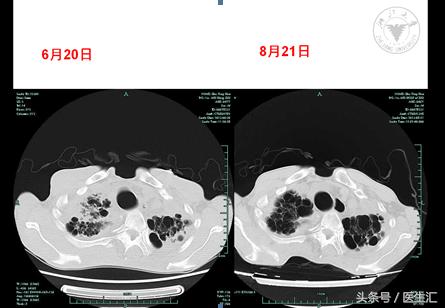

06-20肺CT平扫:

两肺间质性改变,肺气肿,两肺多发肺大泡。两肺上叶慢性感染机化。较2月12日CT大致相仿。

08-21增强扫描(一部位)):慢支、肺气肿伴两肺多发肺大泡;两肺间质性改变,左肺上叶病灶对比6月20日CT,部分病变有吸收好转。左上肺术后改变。两侧胸膜增厚粘连。